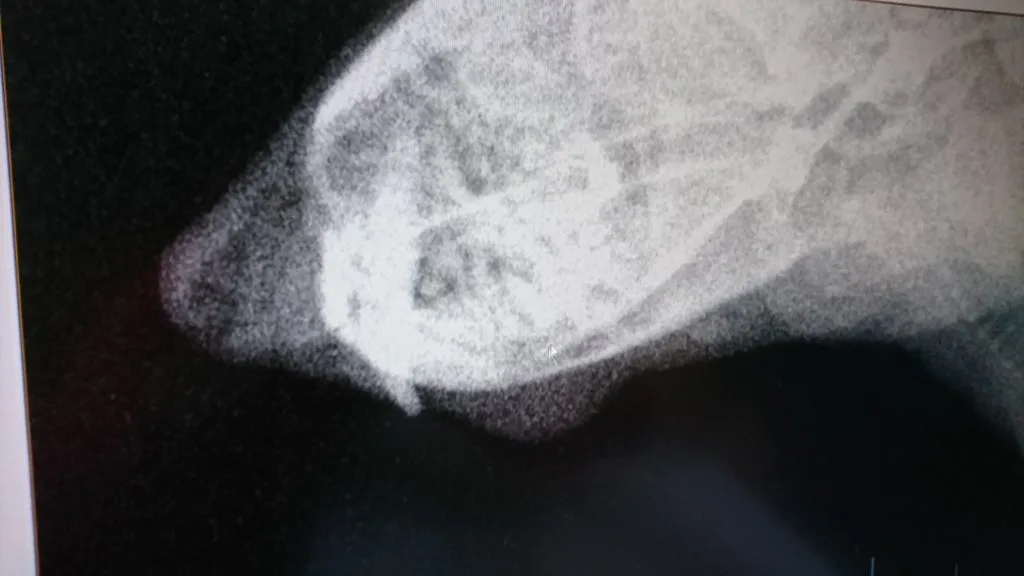

今日のアイキャッチ画像:上の歯にも問題がある事が分かる写真

実は「上の歯も問題がある」と最近になって発覚しました。

正確には下側の問題はもう行き着くところまでいってしまっているから、「今度は上も」と言った方が正しいのかもしれません…

その「問題の上の歯」が少し見えます。

犬歯では無く奥側の歯なので、この部分は「起きてる状態では非常に見えずらい」とされる部分です。

上記の通り、数値的な問題で、もう口の中の事はしてあげられない状態なので、麻酔をかけてまで「見る」機会は私には無いと思っていたのですが、

こうして少しだけ見せてくれました。

炎症が起きないように注意してあげるとともに大事にしてあげたいって思います。